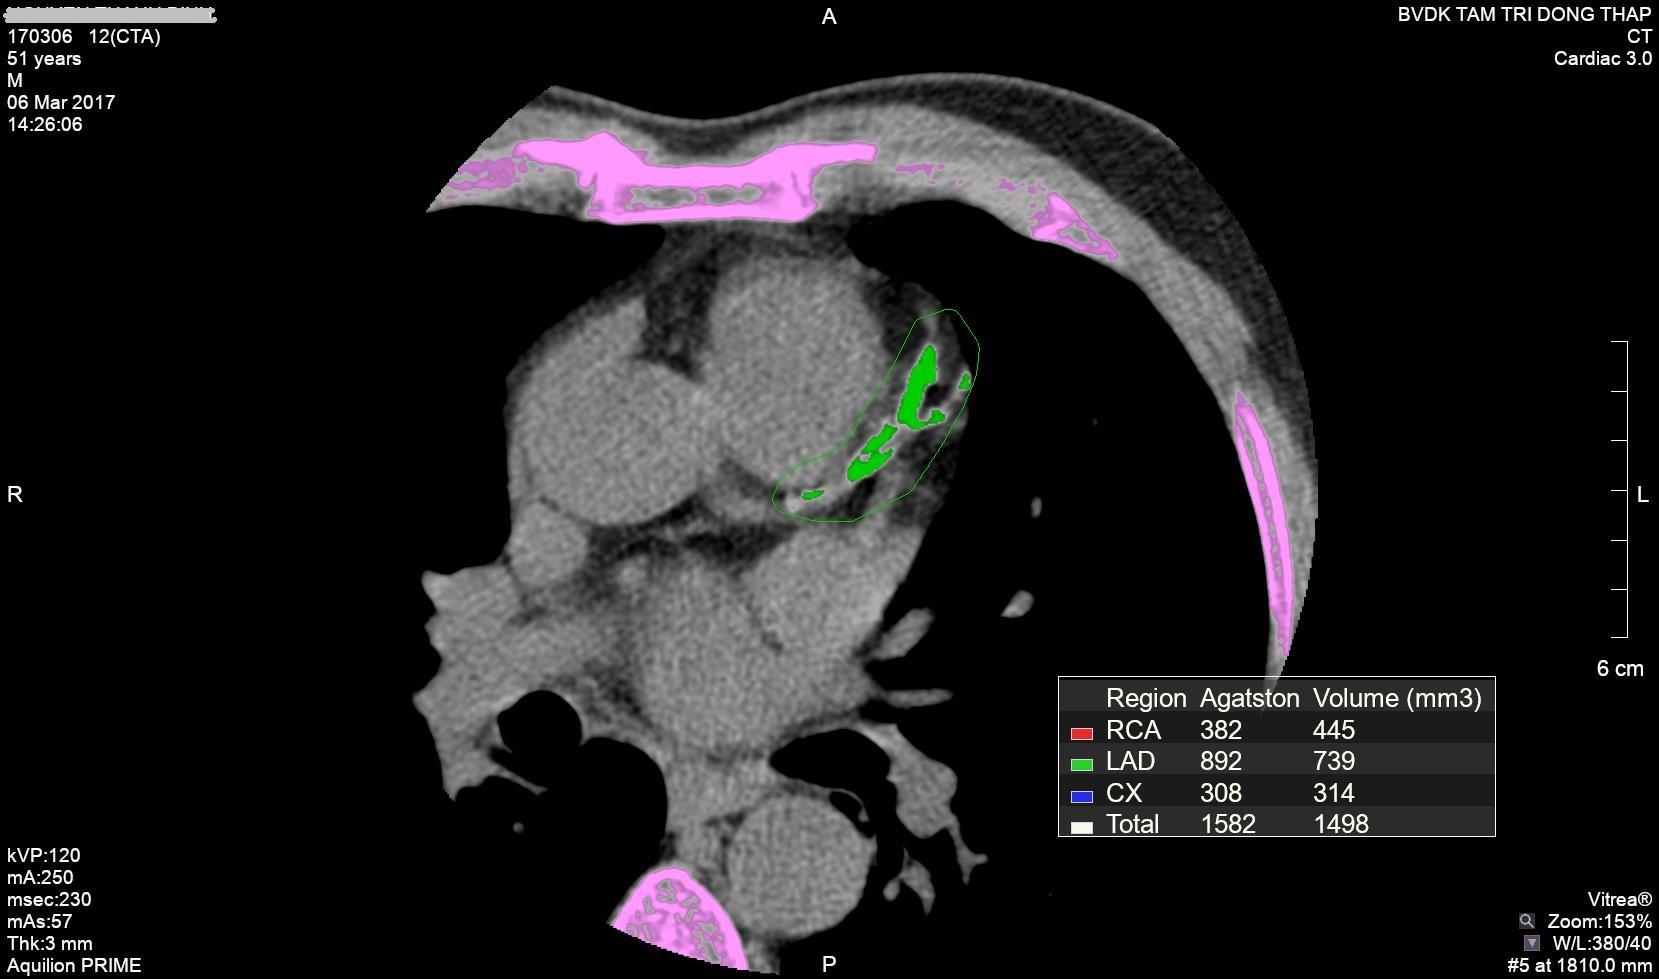

Bệnh viện Đa khoa (BVĐK) Tâm Trí Đồng Tháp đã ứng dụng kỹ thuật chụp CTscan mạch vành từ nhiều năm nay, đã phát hiện nhiều trường hợp hẹp mạch vành ở các mức độ khác nhau, mức độ nhẹ và vừa đã có chế độ phòng ngừa và theo dõi điều trị các yếu tố nguy cơ kết quả rất tốt, bệnh nhân không xảy ra nhồi máu cơ tim cấp; riêng các trường hợp hẹp mức độ nặng đã được can thiệp chủ động cho kết quả rất tốt, chổ hẹp của động mạch vành đã được can thiệp không còn hẹp, lập lại lưu thông tốt, nguyên nhân nhồi máu cơ tim cấp đã được giải quyết một cách chủ động, điển hình như trường hợp ông Lê Thanh T. 52 tuổi (ngụ tại P3, TP.Cao Lãnh, Đồng Tháp) đến chụp CTscan mạch vành, có bệnh cảnh là một tình trạng huyết áp điều trị nhiều năm, thỉnh thoảng có cảm giác mệt ở ngực, ông được chỉ định chụp CTscan mạch vành, kết quả phát hiện chỉ số hẹp mạch vành > 70%, mạch vành hẹp rất nặng, chỉ số vôi hóa rất cao > 1.582 điểm Agaston và vôi hóa ở nhiều vị trí 3 nhánh mạch vành. Bệnh nhân được chỉ định can thiệp mạch vành đặt stent 3 nhánh kịp thời không để xảy ra nhồi máu cơ tim cấp, bệnh nhân trở lại cuộc sống và sinh hoạt bình thường.

Hình ảnh chụp mạch vành từ CTscan 80 lát cắt